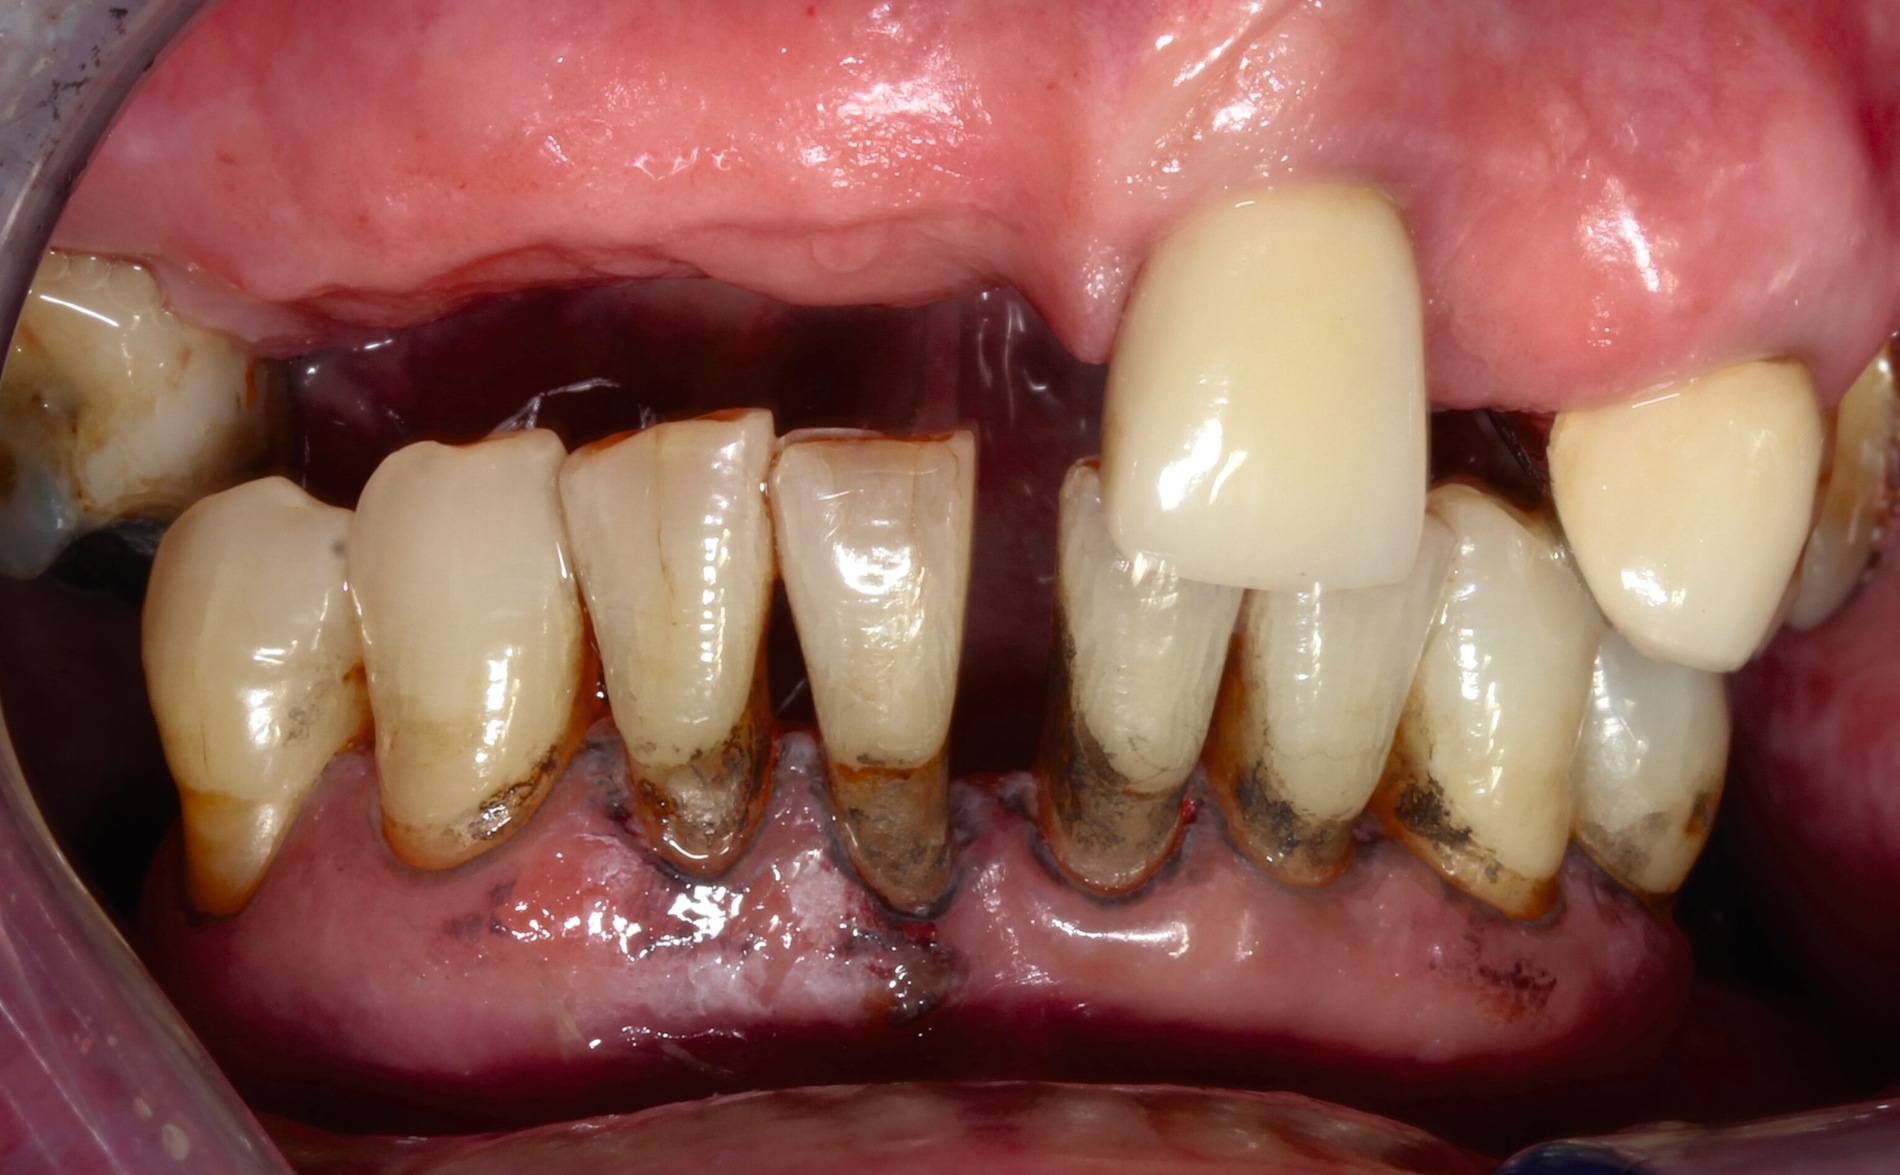

Ist die Läsion aktiv oder inaktiv? Die Beantwortung dieser Frage ist die Ausgangsbedingung für den Therapieentscheid. Wenngleich die Unterscheidung nicht immer einfach ist, ist eine weiche Textur bei Sondieren und eine deutliche Plaquebedeckung ein sicheres Zeichen für Kariesaktivität [Carvalho und Lussi, 2017]. Bei aktiven Läsionen sollten Lokalisation und Ausdehnung genau exploriert werden, was die Behandlungsoptionen wesentlich bestimmt (Abbildung 1). Bei inaktiven Läsionen ist keine restaurative Therapie erforderlich, jedoch sind risikoadaptierte Präventionsmaßnahmen angezeigt.

Bei Läsionen im nicht sichtbaren Bereich sollte jedoch immer der Versuch im Vordergrund stehen, aktive Stadien in inaktive zu überführen. Das setzt die Compliance der Patienten ebenso voraus wie die Zugänglichkeit des entsprechenden Bereichs für Mundhygienemittel. Entsprechende Maßnahmen umfassen die Glättung überhängender Schmelzränder, Verbesserung der Mundhygiene, Anwendung einer 5.000 ppm-Zahnpaste und die bestmögliche Vermeidung kariogener Lebensmittel [Ganß et al., 2023; Meyer-Lueckel et al., 2019; Paris et al., 2020]. Mitunter sind Lebensmittel, wie prozessierte Stärke, die im Bereich des koronalen Zahnanteils nicht oder nur sehr wenig kariogen sind, für die Wurzeloberfläche bei entsprechender Biofilmbedeckung bereits kariesfördernd, so dass im Rahmen der Ernährungsberatung ein besonderer Fokus auf diese Lebensmittel gelegt werden sollte. Eine weitere effektive Option ist die Verwendung von Silberdiamminfluorid (SDF).

Eine bekannte Nebenwirkung bei Anwendung auf kariösen Läsionen ist die Schwarzfärbung des behandelten Bereichs (Abbildungen 3, 4). Verfärbungen können aber auch bei Applikation auf kariesfreien Wurzeloberflächen entstehen, diese sind jedoch mit einer professionellen Zahnreinigung gut zu entfernen (Abbildung 2).

Tatsächlich zeigt die klinische Erfahrung, dass es möglich ist, bei mehrmaliger Applikation innerhalb eines Vierteljahrs auch sehr aktive Läsionen mit taktil weicher Oberfläche trotz eingeschränkter Mundhygiene gut zu erhärten (Abbildung 4). Für die koronale Karies bei Kindern konnte die bessere Wirkung nach wiederholter Anwendung allerdings nicht bestätigt werden. [Smutkeeree et al., 2025].

Der Wirkungsmechanismus ist bislang nicht aufgeklärt. Die wesentlichen Verbindungen in SDF-behandelten Läsionen sind Silberphosphat, Silberoxid und Silbersulfid. Silberphosphat ist ein guter Photokatalysator [Yi et al., 2010], der spezifische chemische Reaktionen mit oder zwischen den verschiedenen beteiligten Verbindungen und Zahnstrukturen induzieren oder aber die auch ohne Licht eintretenden Reaktionen einfach beschleunigen könnte. Es wird vermutet, dass beispielsweise metallische Silbernanopartikel entstehen könnten [Li et al., 2019]. Abbildung 3 zeigt bräunliche Verfärbungen der Schleimhaut nach Lichteinwirkung.